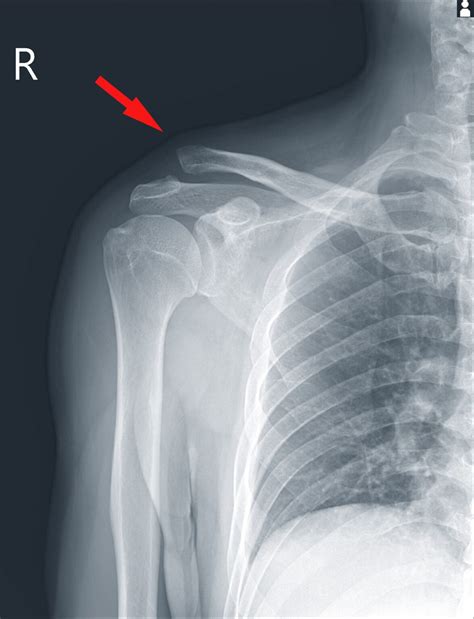

• AC Joint Separation: This occurs when the ligaments supporting the AC joint are torn, often due to a fall or direct impact. It is graded on a scale from I to VI, with higher grades indicating more severe injuries.

• Fractures: Breaks in the clavicle or scapula can be clearly seen on an X-ray. These fractures often result from high-impact injuries.

• Bone Alignment: The bones should be properly aligned. Any displacement or misalignment can suggest a fracture or dislocation.